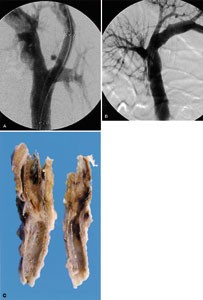

We report a case of mesenteric hematoma following blunt abdominal trauma that was successfully treated with transcatheter arterial embolization (TAE) and did not require surgical repair. A 43-year-old man with blunt abdominal trauma caused in a factory accident was admitted with a stable general condition and laboratory data. On CT examination, a large mesenteric hematoma with extravasation of contrast media was observed. TAE was first attempted to control the bleeding. A superior mesenteric angiogram showed extravasation of contrast medium from a branch of the ileocolic artery and obstruction of the cecal branch. After successful TAE using microcoils, the distal portion of the cecal branch was still preserved via collateral circulation. No abdominal symptoms have occurred during the 7 months following TAE. In mesenteric injury cases with limited intestinal damage, TAE may therefore be a reasonable alternative to emergent laparotomy.

Figure 2

Figure 3

Figure 4